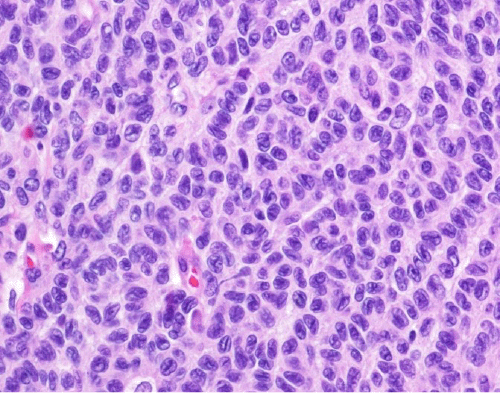

Pathology revealed a 15 × 13 × 10 cm predominantly circumscribed mass with focally infiltrative margins (Figure 2). Histologic assessment of the tumor revealed areas of infarct-like necrosis and hemorrhage. The tumor was composed of cells with indistinct to delicate borders without gland formation with ovoid, grooved nuclei sometimes growing in a distinctive lace-like pattern (Figure 3). The tumor cells had a low mitotic rate without atypical mitosis. Immunohistochemistry was positive for inhibin-alpha, S100, actin, SF1, and pan-cytokeratin with retained INI-1 expression, indicating that the tumor was an adult granulosa cell tumor (GCT). Cytogenetics was negative for abnormalities.

Figure 3. Histologic Section From Tumor Mass. Published with Permission

Note cells with indistinct to delicate borders without gland formation arranged in a trabecular pattern with moderately atypical nuclei with nuclear grooves and small nucleoli